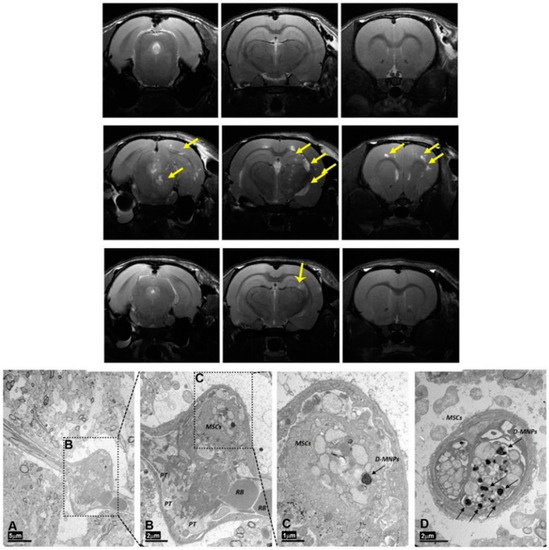

- Argibay, B.; Trekker, J.; Himmelreich, U.; Beiras, A.; Topete, A.; Taboada, P.; Pérez-Mato, M.; Vieites-Prado, A.; Iglesias-Rey, R.; Rivas, J.; et al. Intraarterial route increases the risk of cerebral lesions after mesenchymal cell administration in animal model of ischemia. Sci. Rep. 2017, 7, 40758. [Google Scholar] [CrossRef]

| MRI cell tracking | Superparamagnetic iron oxide nanoparticles (SPIONs) | Cell tracking of mesenchymal stem cells (MSCs) | [97] |